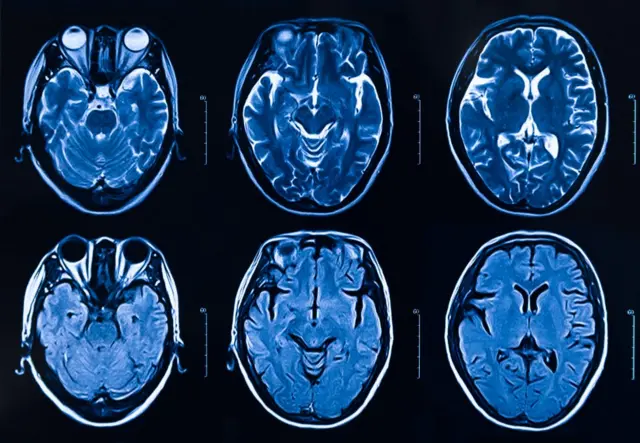

Y aunque reconoce que las resonancias magnéticas funcionales (IRMf) -que permiten visualizar regiones del cerebro al ejecutar tareas específicas- son de gran ayuda para entender aspectos de ese órgano, cuando se trata del agradecimiento no alcanzan a mostrar "todo lo que ocurre en el cerebro".

Fuente de la imagen, Getty Images

"La gratitud es un estado complejo de componentes cognitivos y emocionales que interactúan, por lo que es probable que involucre múltiples sistemas cerebrales. No es tarea fácil aislarlos en un escáner cerebral", le señala a BBC Mundo.

Sin embargo, reconoce que estudios recientes con neuroimágenes ofrecen pistas importantes.

"Al medir la actividad cerebral de los participantes, los investigadores encontraron que la gratitud, al igual que otras emociones complejas, provoca la activación sincronizada en múltiples regiones del cerebro que involucran conceptos sociales, respuestas emocionales y circuitos de placer".

Wong le indicó a BBC Mundo que a los voluntarios también se les hizo estudios IRMf.

Descubrieron que en las personas que habían escrito cartas de gratitud y que sintieron agradecimiento cuando se les tomaron las imágenes por resonancia, hubo "una mayor actividad en la parte del cerebro llamada corteza prefrontal medial, que es un área que está conectada con el aprendizaje y la toma de decisiones".

Las imágenes fueron captadas tres meses después de que las cartas comenzaran.